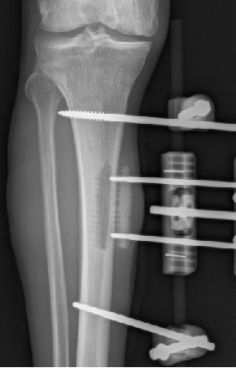

多年来,贵州航天医院各科室紧跟医学前沿,不断强技术、补短板,大力开展新技术、新项目,完成了许多高精尖、高难度、本地区“首例”的技术,填补了医院医疗技术空白,满足了群众日益增长的医疗需求。 贵州航天医院骨科率先在遵义地区开展骨搬移技术,截至目前,已治愈慢性骨髓炎、感染性骨不连、骨缺损、脉管炎、糖尿病足患者200余例,糖尿病足治疗保肢率达到98%。 本期,我们将为大家带来骨科特色技术——骨搬移技术(Ilizarov)。 案例分享 一名59岁的患者,身患糖尿病12年,在来我院3个月前出现了右脚溃烂的症状,来院就诊时,患者的右脚十分红肿,右脚脚趾坏死,伤口处不断流出黑红色脓液,情况十分严重。在接诊到患者时,骨科专家团队高度重视,立刻为患者完善了CT血管造影(CTA)等相关检查,诊断为:2型糖尿病,糖尿病周围血管病变,右糖尿病足。 术 前 考虑到患者情况比较严重,为最大限度保证患者肢体完整,科室专家团队进行了严格的讨论评估,为患者制定了骨搬移技术治疗方案,在征得患者及其家属的同意后,成功通过搬移骨块为患者进行治疗,促进患者病变肢体血管再生。 胫骨横向骨搬移外架固定 清除感染病灶 术后调节外架,通过搬移骨块 促进患肢血管再生 患者在术后三周前来换药,观察到感染得到进一步控制;术后六周复查,患者病变处已愈合,进行CT血管造影(CTA)后可明显观察到足部血管再生。 术后3周 术后6周愈合 CT血管造影见足部血管再生 糖尿病患者全身与局部的问题互为影响,形成恶性循环,糖尿病足溃疡创面迁延不愈,常见干性坏疽、湿性坏疽、趾坏死、深且大的溃疡以及骨髓炎等症状,还可导致脓毒血症,以往为保全生命,患者被迫选择一次或多次截肢。骨搬移技术的发展进步,能在血糖有效控制、局部有效清创下,有效促进患肢微血管再生,改善患肢血供,达到糖尿病足更快治疗康复的目的,并能根据病变情况最大限度的保障患者肢体完整。 什么是骨搬移技术 骨搬移技术是通过使用专用的骨外固定器固定骨段,每天缓慢牵拉,在牵拉搬移过程中,骨段尾部形成新骨及新的软组织,从而修复骨骼缺损及软组织缺损。是治疗大段骨缺损、骨不连、骨感染、肢体畸形的金标准方法,也用于治疗脉管炎、糖尿病足等肢体缺血性疾病。 骨感染缺损 切除感染段 搬移骨段 新骨形成 骨感染根治愈合 骨搬移技术原理 生物组织在持续、稳定、缓慢牵拉下,能刺激细胞分裂、组织再生,骨外固定技术运用该原理,通过持续缓慢调节外固定器形成牵拉张力,促进牵引成骨与相邻组织再生,如神经、血管、肌肉、皮肤等再生,达到治疗大段骨缺损、肢体缺血如糖尿病足等疾病的目的。 骨搬移技术优势 (一)除治疗骨缺损、骨不连外,有更广的适用范围,利用组织再生、血管再生等特性,能大量运用于肢体畸形的矫形、糖尿病足等的治疗。 (二)治疗效果确切,重建肢体外型和功能,极大降低截肢率和残疾率。 (三)明显提高了患者生活质量,极大减轻其家庭及社会负担。 肢体畸形的矫形 慢性骨髓炎 骨段切除 术后1年 濒临截肢的脉管炎术后6周 难愈创面术后3周 贵州航天医院骨科 专家团队 赵学平 骨科主任 主任医师 临床擅长:从事骨科临床工作30余年,对骨科常见疾病的诊治具有丰富的临床经验。 世界中医药联合会脊柱康复专业委员会常务理事,中华中医药学会整脊分会常务委员,中国中西医结合学会骨伤科分会肢体矫形功能重建与康复专家委员会常务委员,中国研究性医院学会骨科创新与转换专业委员会关节外科学组保髋工作委员会常委,中国康复技术转化及发展促进会骨外科与康复技术转化专业委员会常务委员,泛珠三角区域运动医学联盟(PPRD-SMA)理事会常务理事,中国研究型医院学会运动医学专业委员会委员,贵州省中医药学会整脊分会副主任委员,贵州省中西医结合学会银质针专业委员会副主任委员,贵州省康复医学会骨与关节专业委员会常务委员,贵州省人民医院骨科专科联盟常务理事,贵州省康复医学会骨内科专业委员会常务委员,中华医学会贵州省骨科学会委员,贵州省康复医学会脊柱脊髓专业委员会常务委员,贵州省运动医学分会委员,贵州省康复医学会骨与软组织肿瘤专业委员会委员,遵义市医学会创伤分会副主任委员,贵州省康复医学会骨内科专业委员会遵义地区分会常务委员,遵义市医疗事故鉴定、伤残鉴定、工伤鉴定、司法鉴定专家。 长期从事骨科临床研究及教学工作,在国家级、省部级杂志发表论文20余篇,SCI论文2篇,参与主编骨科专著2部,主持省部级科研项目2项,参与指导省部级、市级科研项目6项。 陈明勇 骨科副主任 副主任医师 临床擅长:从事创伤骨科工作约20年,对骨缺损、骨不连、骨肿瘤、肢体畸形等的肢体矫形重建及功能重建,慢性化脓性骨髓炎的根治治疗、糖尿病足的保肢治疗、快速康复理念(ERAS)下的老年骨折的诊治,四肢复杂骨折的诊治,四肢骨折等微创手术治疗具有丰富的临床经验。 2004年毕业于遵义医学院临床专业,曾在中国人民解放军总医院、广西医科大学第一附属医院、上海第六人民医院骨科进修。中国中西医结合学会骨伤科专业委员会横向骨搬移治疗糖尿病足及微血管网再生学组首届委员,遵义市医学会创伤分会常务委员。 瞿 辉 骨科 副主任医师 临床擅长:对骨科的常见病、关节外科、脊柱外科及运动医学疾病的诊治具有丰富的临床经验,熟练掌握骨科手术操作技术。 毕业于遵义医学院临床医学系,2005年前往广州中山大学第一附院骨显微医学部进修学习,2011年前往成都华西医院进修学习,并多次在省内外学习骨科相关知识,是中华医学会骨科分会会员。 赵兴东 骨科 主任医师 临床擅长:擅长骨科的常见病及各种创伤、四肢骨折创伤修复、骨感染、手足疾病的诊治和手足体表畸形的矫形整复,熟练掌握骨科四肢骨病及创伤的手术操作技术,尤其在四肢关节复杂性损伤、手足外伤、组织缺损创面、难治创面的皮瓣修复方面及平足、高弓足矫形方面及四肢慢性疼痛诊治、康复方面具有丰富的临床经验。 硕士研究生,毕业于遵义医学院临床外科系,2015年前往山东省立医院手足外科进修学习;遵义市医学分会创伤分会第一、二届委员,遵义市手外科医学会第二委届员会常务委员;在省级及省级以上期刊发表文章9篇,参编著作2部,参与主持并完成市级课题1项,参与市级课题2项、省级课题1项。 张俊凯 骨科 副主任医师 临床擅长:从事骨科临床工作28年,对创伤骨折、骨感染、骨缺损、骨不连等外科诊治,四肢骨折的微创手术治疗,四肢复杂骨折(如关节内粉碎性骨折、多发骨折等)的损伤控制及手术治疗等具有丰富的临床经验。 1995年毕业于遵义医学院临床专业,2009年前往复旦大学附属医院骨科进修1年。 卢懿明 骨科 副主任医师 临床擅长:从事骨科工作18年,对创伤骨折、四肢骨折的微创手术治疗、四肢复杂骨折(如关节内粉碎性骨折、多发骨折等)的损伤控制及手术治疗,尤其是髋部骨折的PFNA等微创技术,踝关节骨折、膝关节周围骨折的Mipo微创技术等具有丰富的临床经验,开展了4项新技术,发明6项新型专利技术。 2005年毕业于遵义医学院临床专业,2017年,前往南方医科大学第三附属医院骨科进修半年,回院后运用Mipo技术对骨干骨折及干骺端骨折的治疗技术,同时积极开展骨盆骨折、髋臼骨折腹直肌外侧切口的应用;发表了多篇专业论文,经常参与省内外学术交流会授课,获得医院荣誉称号多个。 邬夏荣 骨科 副主任医师 临床擅长:从事骨科工作16年,对四肢复杂骨折、骨肿瘤的诊治,尤其是足踝创伤、慢性踝关节损伤、平足症等诊疗具有丰富的临床经验。 2006年毕业于遵义医科大学临床医学专业,曾在陆军军医大学西南医院进修学习,发表多篇骨科学术论文。 余德怀 骨科 副主任医师 临床擅长:从事骨科工作10余年,对运动医学、骨关节、脊柱外科常见病、多发病的诊治具有丰富的临床经验。 硕士研究生,2011年毕业于遵义医学院临床医学专业,曾前往遵义医科大学附属医院运动医学专业进修学习;是贵州省医学会运动医学分会青年委员,西部关节镜联盟委员;发表多篇骨科学术论文。 冯 乾 骨科 副主任医师 临床擅长:从事骨科工作近20年,熟练掌握骨科多发病及常见病的诊治,尤其对脊柱退变性疾病的诊断及治疗具有丰富的临床经验,主要研究脊柱微创相关治疗方式,能熟练开展椎间孔镜及VBE。 曾前往北京大学第三医院进修学习疼痛及椎间孔镜、首都医科大学友谊医院专业进修脊柱内镜;是贵州省康复医学会第三届脊柱脊髓专业委员会委员;发明专利3项、发表脊柱外科专业论文多篇。 张艳金 骨科 副主任医师 临床擅长:从事骨外科工作16年,对复合伤、多发伤的救治、四肢骨干骨折、关节周围骨折、骨肿瘤、骨髓炎等诊治具有丰富的临床经验。 中共党员,硕士研究生,2006年本科毕业于山西医科大学第二临床医学院,2011年研究生毕业于北京军区总医院;在“老年COPD患者合并髋部骨折的诊治”国际合作课题组研究两年,在老年髋部骨折的诊治方面具有丰富的经验,并发表论文6篇;承担遵义市级课题1项;承担遵义医科大学的临床教学工作,获得遵义医科大学优秀带教老师荣誉。编撰有《骨科疾病诊疗精粹》一书,开展2项新技术,编撰地方规范《务川自治县创伤骨科常见疾病诊疗规范》一书。 赵小锋 骨科 副主任医师 临床擅长:从事骨科临床工作11年,对骨科常见病、多发病诊疗有较为丰富的临床经验,擅长脊柱相关疾病诊断及治疗,尤其是颈、腰、腿疼痛疾病诊断及治疗,擅长胸腰椎骨折微创经皮穿刺内固定术、经皮穿刺椎体成形术、经皮穿刺脊柱内镜下腰椎间盘摘除术、单纯开创腰椎间盘摘除术、腰椎滑脱复位椎间植骨椎融合内固定术、腰椎管狭窄减压融合内固定术及人工髋、膝关节置换术等。 2012年毕业于遵义医学院外科学专业硕士研究生,2019年参加“遵义市115医学人才精英计划”于上海交通大学第一附属医院培训学习,2023年于北京大学第三人民医院脊柱外科进修学习,曾获得遵义市优秀医师荣誉称号。 遵义市手外科第一届委员,遵义市医学会创伤分会第一届委员,遵义市医学会创伤分会第二届委员,贵州省康复医学会第三届脊柱脊髓专业会委员,遵义市医学会烧伤与整形外科学分会委员,发表论文5篇,其中国家级核心期刊1篇,SCI论文1篇,主持市级课题1项并结题,参与市级课题2项。 贵州航天医院骨科简介 基本情况 贵州航天医院(原3417医院)骨科组建于1968年,前身是以创伤和断肢(断指)再植闻名于世的上海市第六人民医院骨科,中国断肢(断指)再植的奠基者、中科院院士陈仲伟等著名专家、学者多次莅临科室指导医疗、教,是贵州省最早拥有专业骨科技术科室之一,在70年代开展了贵州省首例断肢(断指)再植手术。组建50余年来,诊治患者已逾百万,挽救了无数的伤病员,成为了保障遵义地区人民群众健康的重要支撑。 经过几代人的不懈努力,今天的骨科,已由创伤骨科发展至骨病、骨肿瘤、骨结核等领域,现有脊柱外科、关节外科、四肢创伤、手足外科四个亚专科,成为了集医疗、教学、科研于一体的综合学科,是贵州省临床重点专科、遵义市临床重点专科、遵义市骨科临床医学中心、遵义市基层骨科专科联盟理事长单位。 科室目前开放床位110张,共有医护人员50余人,副高级以上专家18人,硕士研究生15人。拥有一流骨科医疗设备多台,每年不定期选派优秀技术骨干到全国各大知名医学院校进修、学习、参观、交流,并邀请国内、国外知名专家教授来院进行交流、指导,通过不断引进国内外先进的诊疗技术,科室医疗技术水平稳步提升,为广大人民群众提供了优质的医疗服务。 专科特色 骨一科 (一)骨缺损、骨不连的肢体与功能重建 胫骨横向骨搬移技术治疗糖尿病足: (二)慢性骨髓炎的根治治疗 (三)肢体缺血性疾病如糖尿病足、脉管炎的保肢治疗 (四)皮瓣修复 (五)复杂创伤的治疗 (六)老年髋部骨折及小儿骨折快速手术 老年髋部骨折: 骨二科 (一)胸腰椎骨折微创经皮椎弓根螺钉固定术 (二)老年性骨质疏松性患者腰椎滑脱脊柱内固定术(骨水泥螺钉) (三)V形双通道脊柱内镜技术(VBE)腰椎融合术治疗腰椎退行性疾病 (四)老年性骨质疏松性骨折(PVP/PKP)术 (五)人工髋关节置换术 (六)双侧股骨头坏死人工全髋关节置换 (七)右侧全髋置换术后假体周围骨折翻修 (八)人工膝关节置换术 (九)人工膝关节假体松动翻修 (十)关节镜技术 传统手术切口 关节镜技术切口 诊疗范围 骨一科 1.四肢创伤、矫形。 2.手、足踝外科。 骨二科